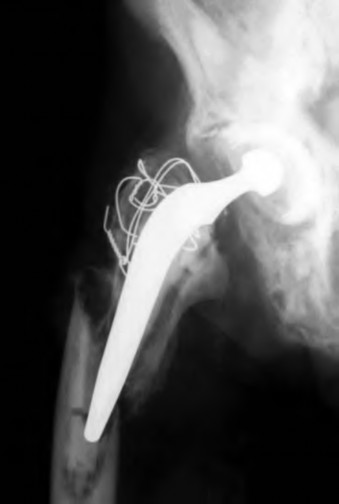

A 62-year-old woman presents for her 1-year follow-up after a revision right total hip arthroplasty. She has no complaints of pain and has returned to all her activities of daily living. An AP radiograph is shown in Figure A. The black arrow in the radiograph indicates she is at higher risk for which of the following?

5) Catastrophic ceramic bearing failure

The radiographs reveal a constrained system by the metal ring of the constrained liner, and subsequent broken ring representing a dissociation of the liner. Ring failure is associated with increased risk of hip dislocation. The incidence of dislocation ranges from 0.5% to 10% after primary and up to 28% after revision THA. Procedures described to treat this instability include reorientation of femoral or acetabular component position, trochanteric reattachment or advancement, capsulorrhaphy, the use of an elevated acetabular liner, conversion to a bipolar prosthesis, lengthening of the femoral neck, resection arthroplasty, or the use of a constrained acetabular component.

In the Level 4 study by Shapiro et al, 85 constrained THAs were implanted during revision THA for chronic instability. There was a 2.4% dislocation rate in this cohort and both of these were secondary to constrained liner dissociation. Illustration A shows a radiograph of a constrained hip dislocation secondary to

fracture of the constraining ring on the neck of the liner. An example of a broken constraining ring is shown in Illustration B.